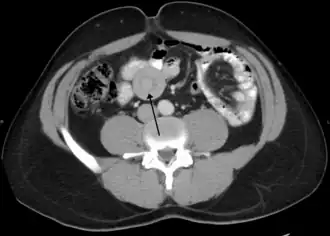

Инвагина́ция кише́чника  — выделяемый в отдельную нозоформу вид непроходимости кишечника, причиной которого является внедрение одной части кишечника в просвет другой[3].

Наиболее часто наблюдается инвагинация в области илеоцекального угла (более 95 %).